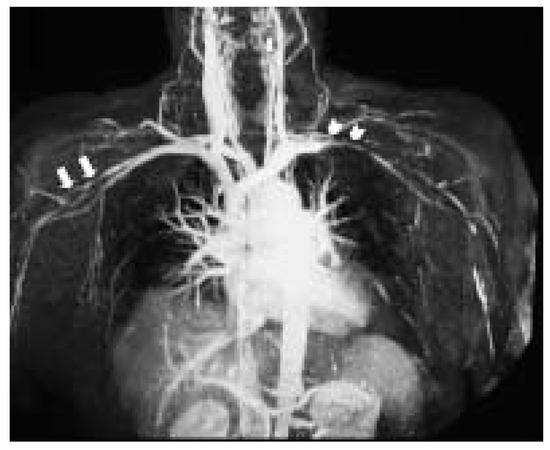

Subclavian and Axillary Giant Cell Arteritis After Influenza Vaccine

by Marcello Di Valentino, Rolf Wyttenbach, Mario Alerci, Jeanne-Marie Segatto, Felix Mahler, Guido Mariotti and Augusto Gallino

Case report A 64-years-old women with history of rheumatic polymyalgia 11 years before developed sub-acute bilateral claudicatio at both arms few days after injection of influenza vaccine (Fluvarix®) [...] Full article